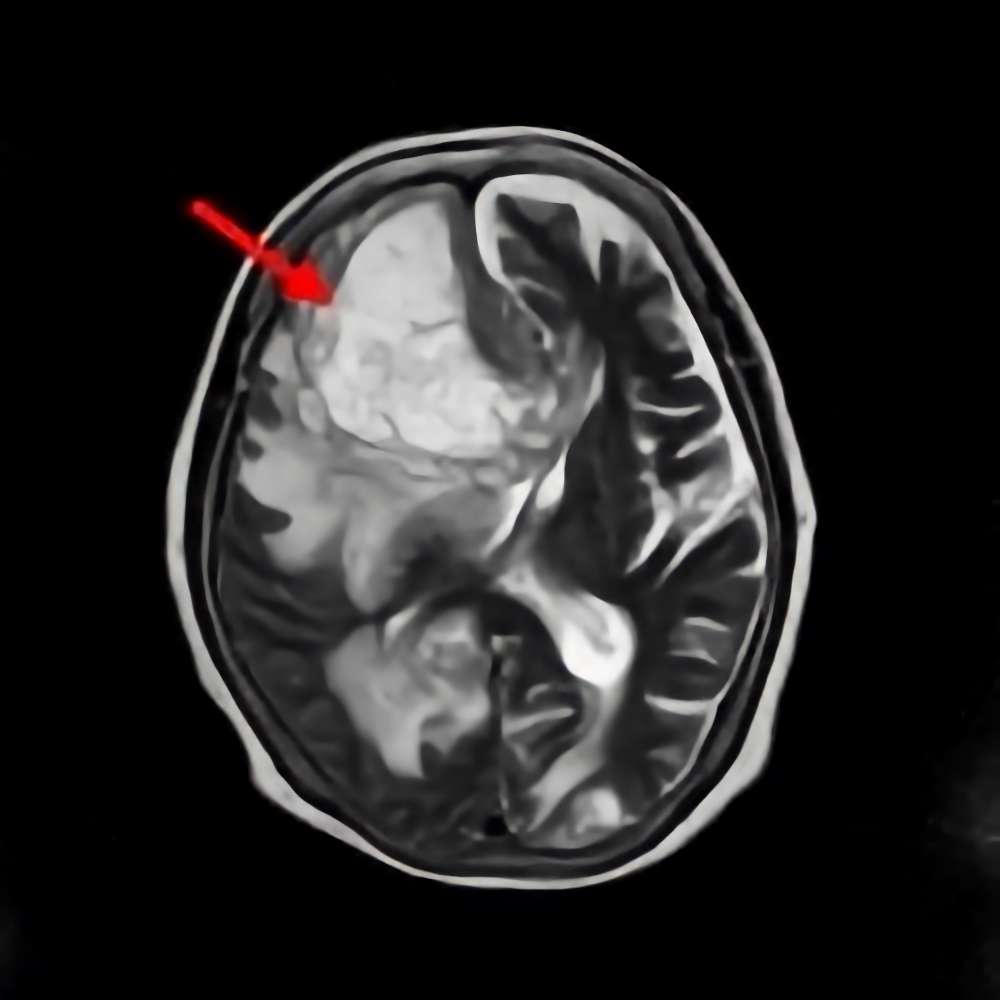

30代

海綿状血管腫

No.’15_49 手術前1

No.’15_49 摘出 前

No.’15_49 摘出 後